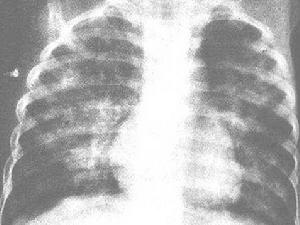

發病緩慢,病程較長,常遷延數月或數年不愈。臨床症狀主要為疲乏、食慾減退、體重減輕及低熱、咳嗽等。初為乾咳,以後有少量白色粘痰,偶帶血絲,咳嗽多於晚間加重,常伴有哮喘發作。肺部可聞乾性囉音,偶有濕性囉音。部分病例出現全身淺表淋巴結輕度腫大及肝臟腫大,在兒童中尤為明顯。偶有脾臟腫大。末梢血液嗜酸性粒細胞明顯增多,血沉增快。約半數病例的血清瓦瑟曼氏反應出現暫時性陽性,血清絲蟲補體結合試驗常呈陽性。肺部 X射線檢查顯示肺紋理增強,有時可見粟粒狀陰影及肺門陰影增寬。診斷時需與過敏性肺炎或勒夫勒氏綜合徵鑑別。砷劑或海群生治療有特效,大劑量左旋咪唑也有效。